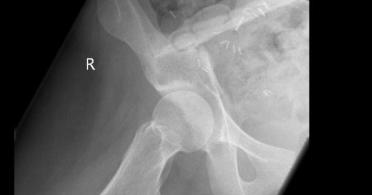

vermelden. Ich erinnert euch alle an die Bilder, die wir euch nach der Operation gezeigt haben. Hier ist es auf dem Foto noch einmal zu

sehen. Es ist ihr operativ das rechte Wadenbein aus dem Bein entfernt und als Stütze in das Becken eingesetzt worden, dort, wo vorher

die Beckenschaufel war. Das ist schon ein Meisterwerk ärztlicher Kunst gewesen. Und Gott hat Gelingen und Segen dazu gegeben. Die

Schmerzen, die Puschel in den letzten Tagen mehr hatte als sonst, rühren jetzt daher, dass der Knochen etwa an der Stelle, auf die der

Pfeil zeigt, richtiggehend durchgebrochen ist. Die Ärzte sprechen von einem Ermüdungsbruch. Der Knochen ist in der Substanz während

der Zeit der Chemo und der dadurch beabsichtigten Verhinderung der Neubildung von Zellen (Zielpunkt waren natürlich die

Krebszellen) zurückgegangen und ermüdet. Das große Problem ist, dass nun noch weniger Stabilität da ist und der Knochen erst wieder

zusammenwachsen muss. Darum werdet ihr, wenn ihr hier reinschaut, nun wieder mehr Bilder von “Puschel im Liegen” sehen. Das ist